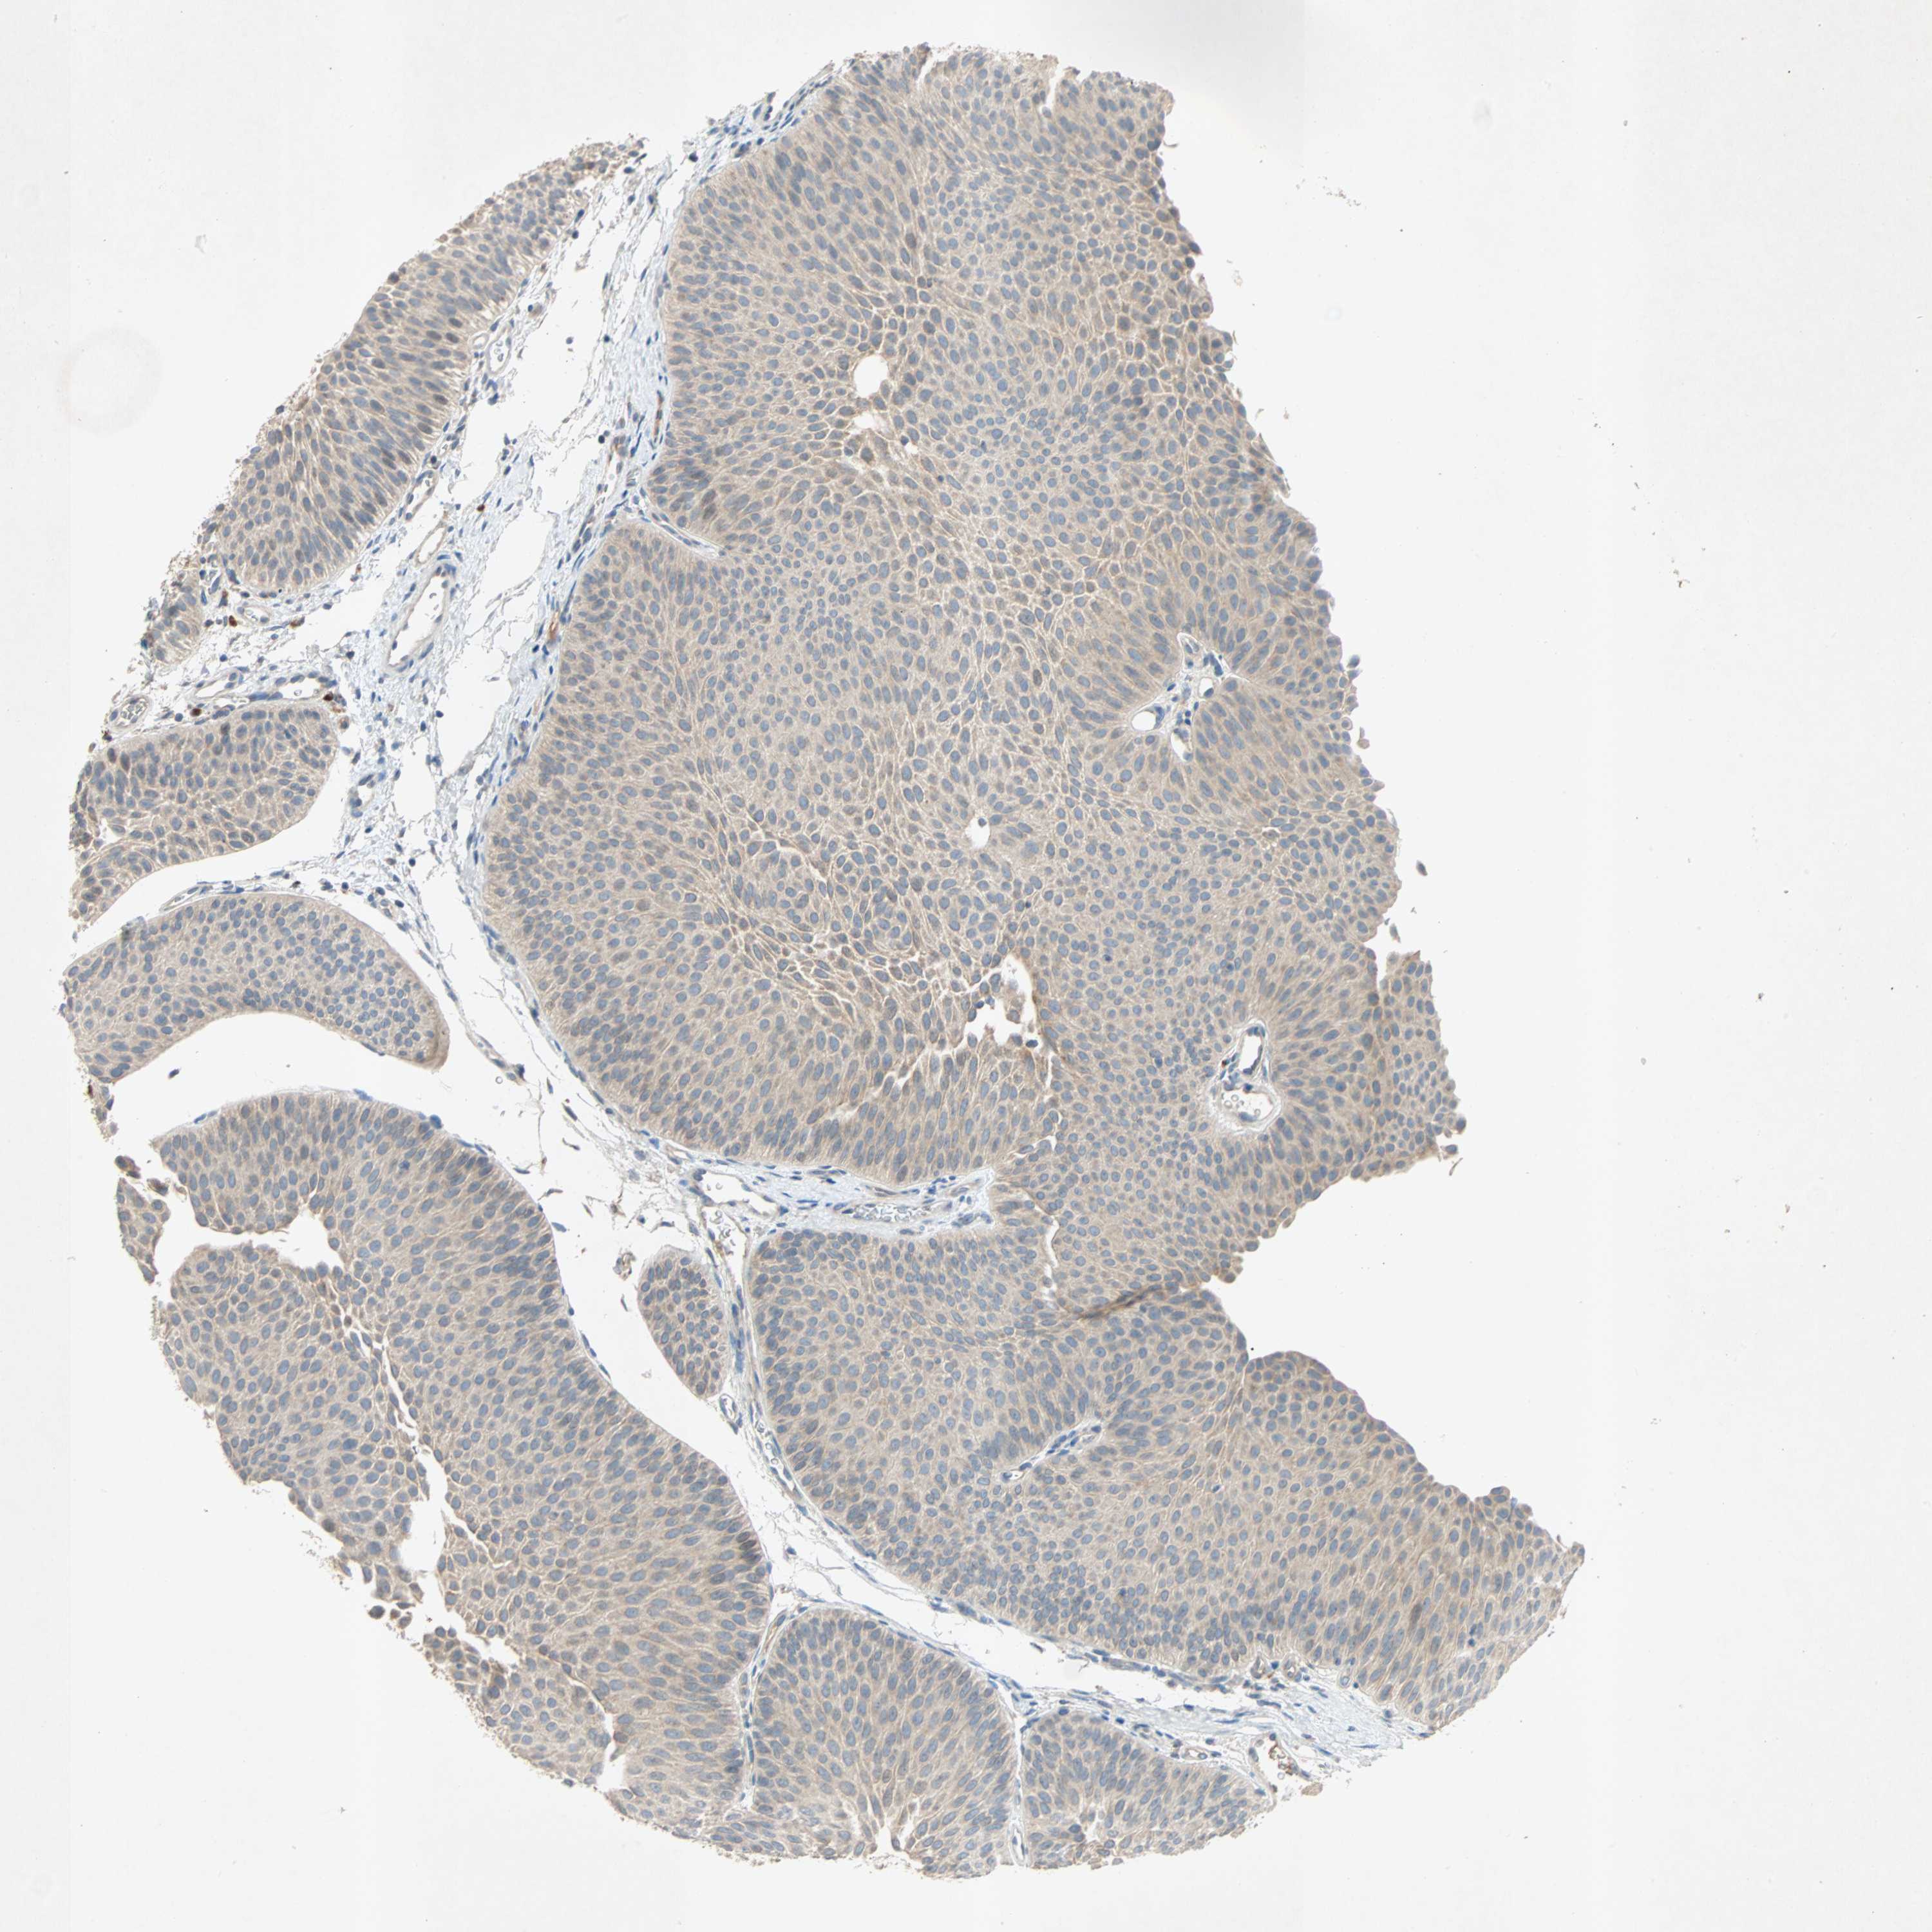

UROTHELIAL CANCER - Protein expressioni

A mouse-over function shows sample information and annotation data. Click on an image to view it in a full screen mode. Samples can be filtered based on level of antibody staining by selecting one or several of the following categories: high, medium, low and not detected. The assay and annotation is described here.

Antibody stainingi

Antibody staining in the annotated cell types in the current human tissue is reported as not detected, low, medium, or high, based on conventional immunohistochemistry profiling in selected tissues. This score is based on the combination of the staining intensity and fraction of stained cells.

Each image is clickable and will lead to virtual microscopy that enables deeper exploration of all samples and also displays staining intensity scores, fraction scores and subcellular localization as well as patient and tissue information for each sample.

Antibody HPA007478

Antibody HPA007966

Urothelial carcinoma, Low grade

Urothelial carcinoma, High grade